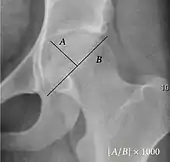

| Measurement | Image | Target | Normal value |

|---|---|---|---|

| Acetabular depth ratio | ![]() |

Deepness of acetabulum. | >250

|

| Center-edge angle of Wiberg | ![]() |

The superior-lateral coverage of the femoral head. | |

| Reimer's migration index[9] | ![]() |

The percentage of the femoral head that lies outside of the acetabular roof. It is also called the femoral extrusion index. | <25% |

| Tönnis angle | ![]() |

Slope of the sourcil (the sclerotic weight-bearing portion of the acetabulum) | 0 to 10°

| Caput-sourcil angle[12] | ![]() |

Superior to the Tönnis angle in cases without joint space narrowing or subluxation.[12] The medial point of the sourcil is defined as being at the same height as the most superior point of caput femoris. | −6 to 12°[12]

| Sharp angle | ![]() |

Acetabular slope | <45°

| Cervical diaphyseal angle | ![]() |

The angle formed between the femoral neck and femoral diaphysis | 120° to 140°